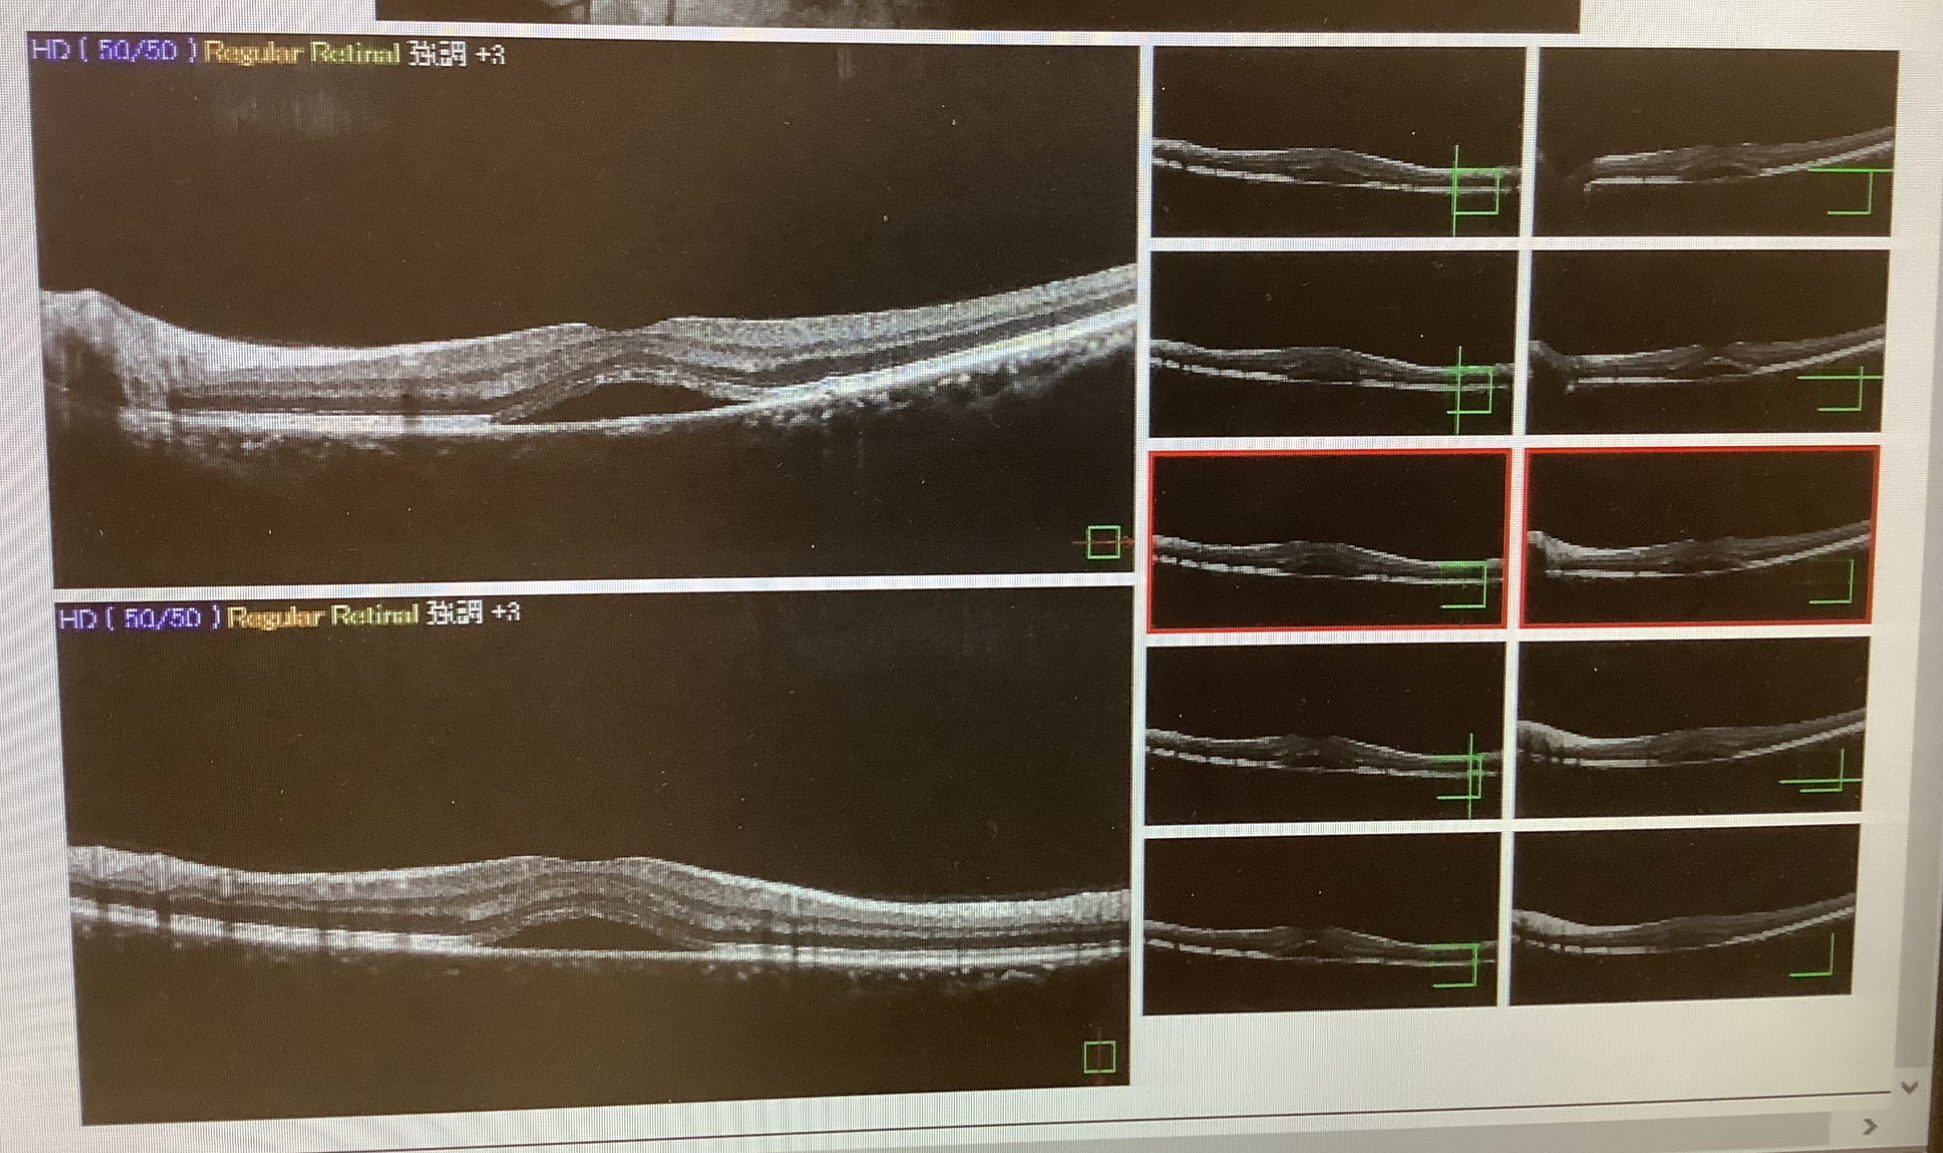

『2〜3年前から左眼の歪みがある』と初診でいらした30代後半の男性は、網膜の中心部の黄斑の下に水が溜まっている所見があり、中心性漿液性脈絡網膜症(CSC)という病気が疑われました。

この病気は網膜の一番内側の網膜色素上皮という層になんらかの障害が現れ、網膜の下の脈絡膜という部分から水が滲み出てきて、黄斑に浮腫みを起こし、歪みや視力低下という症状を引き起こす病気です。